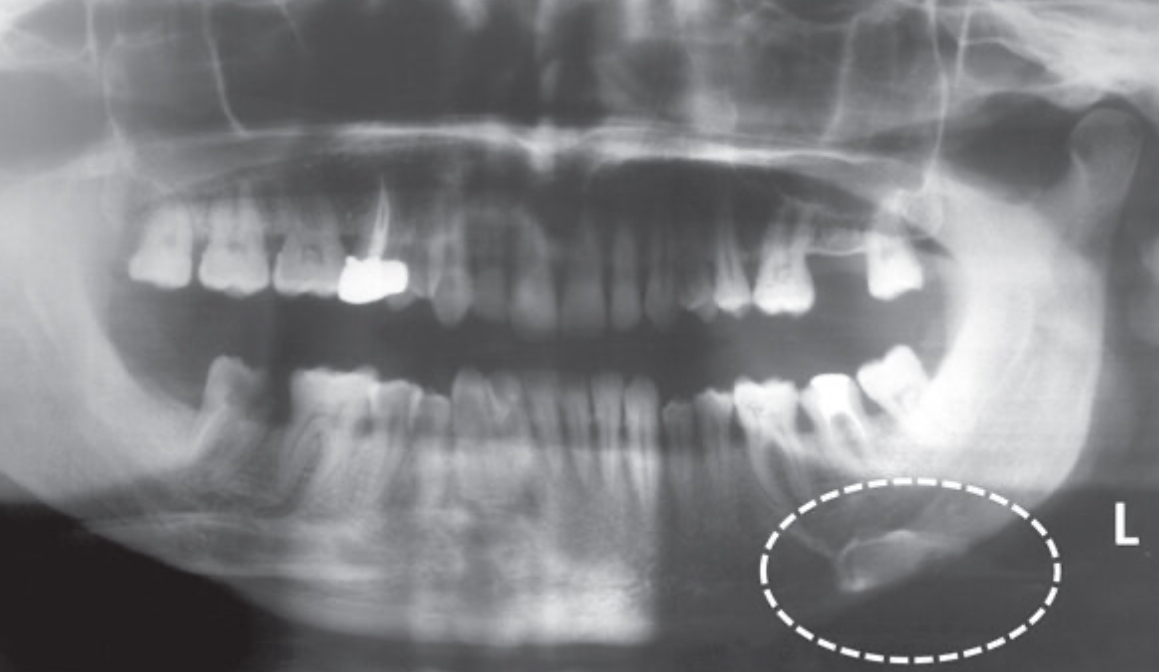

Mandibular Retromolar pad

Hyoid bone

Sometimes appears as a ghost image above the mandible